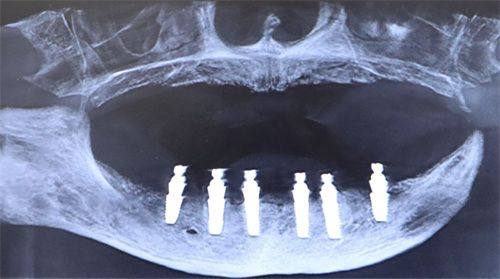

方案确定后,就进入到实际的手术操作阶段了。首先是制备种植窝,医生会根据预先设计的模板,在你的颌骨上进行操作。这个过程中,医生会根据你的牙槽骨厚度、密度等因素,选择合适的种植体和系列钻。就像在合适的土地上选择合适的种子一样,合适的种植体才能更好地在你的口腔中“扎根”。

种植窝制备好后,医生会将种植体植入其中,然后使用特制工具将其旋紧,确保种植体的稳固性。这一步就像是把种子种进土里并固定好。植入种植体后,医生会对创口进行缝合,这样做是为了减少出血和感染的风险,同时促进创口的愈合。